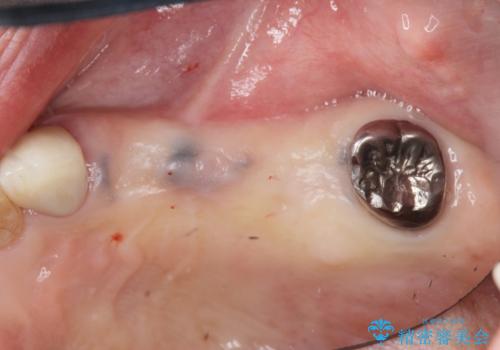

- 歯のないまま放置していた左上奥歯の咬合機能回復を求めて来院されました

咬合力が強く、入れ歯では周囲の歯も欠損状態になることが予想されたので、しっかりと咬合機能の回復のできる

インプラント治療を行うこととしました。